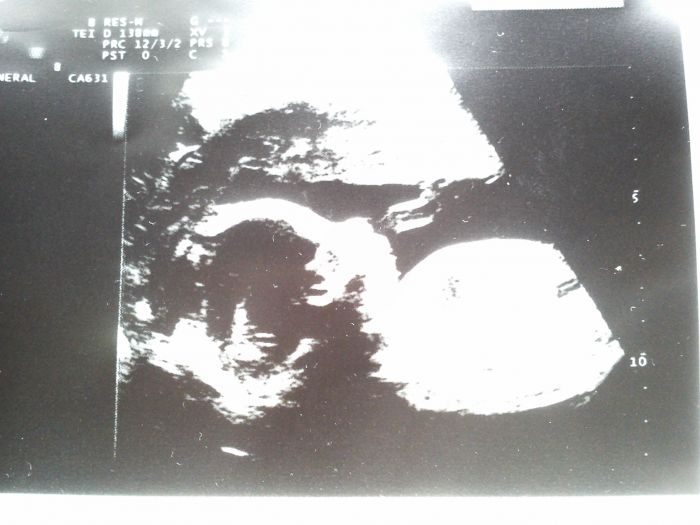

Ahoj holky :-). Jeee Tomáška už máme ve 4d nebo co to je za formát. :-) to je super. :-) hoví si tam moc pekne a malá od Míšky teda si taky umí pohovět. :-D je to klabý. Já mám ze včera taky tak přiložím. Též je to z 21+1 ale doktor byl dost nemocný a tak jsem ho nechtěla otravovat lepší fotkou. Zkusil to vzít a já řekla beru. :-D takze tam není ani celej. Můj přítel říkal ,že už má nahoře vlasy :-D:-D:-D takový číro . Jestli je to pravda nevím ,ale všimla si toho i kamarádka. Že to vypadá jak když má už vlasy. :-D jinak ten můj jeník je prostě hodnej. Skoro o něm nevím. Asi ticho před bouři. :-D